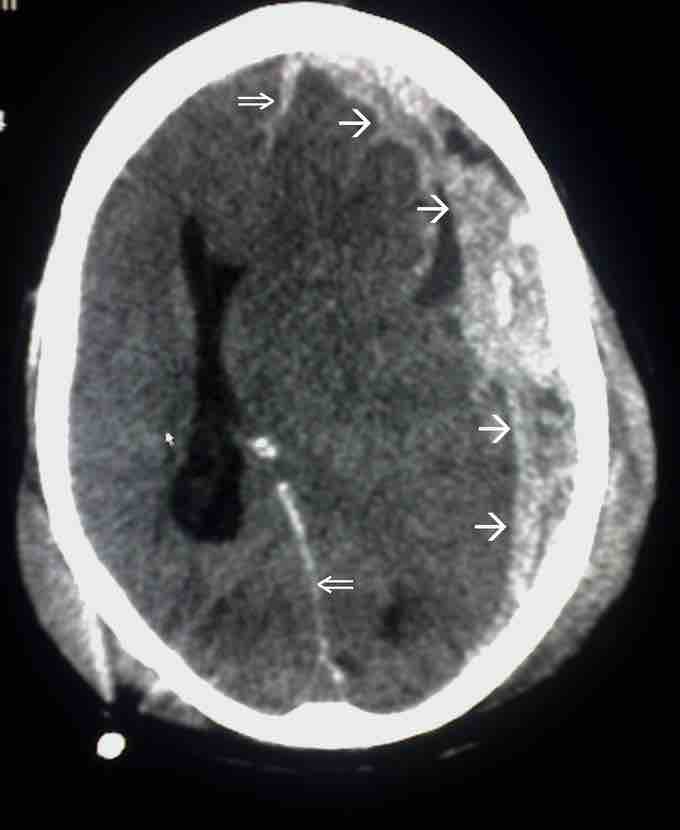

Subdural hematoma is a possible result of traumatic head injury

In this image, the single arrow marks spread of the subdural haematoma and the double arrow marks the midline shift.